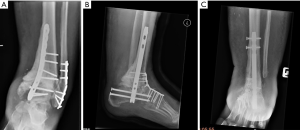

Time from surgery till breakage

The time to hardware failure was found to be very variable in our patient group. The timings of the failure have been categorized into the following groups and included in Table 5: breakage before 3 months, between 3 and 6 months, between 6 and 12 months and after 12 months postoperatively (Figures 5,6). All nail breakage happened after 12 months. Table 1 lists the number of months until failure for each patient.

The patients who had clinically stable feet and were able to ambulate in shoes had a lower mean time for hardware failure compared to those that we considered less stable (patients that needed a cast or an orthosis). The average breakage time for the shoe-group was 9.44 months (SD =7.30), while it was 16.73 months (SD =6.94) for the cast/orthosis-group. This difference was statistically significant (P=0.036).

Patterns of plate breakage

Fourteen out of the 18 broken plates were positioned on the dorsomedial aspect of the foot. Six of these broke at the ankle level and 8 at the talonavicular level. Nine out of the 18 plates that broke were used in bridging mode and 9 in neutralization mode.